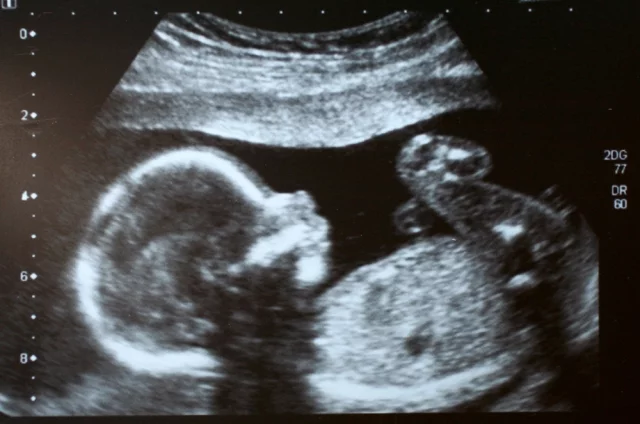

В программу ОМС включены новые услуги, которых ранее в ней не было. Например, неинвазивный пренатальный тест для беременных — безболезненный метод определения хромосомных аномалий у плода теперь доступен бесплатно для всех застрахованных. Тест, который раньше женщины оплачивали за свой счет, теперь можно сделать по ОМС.